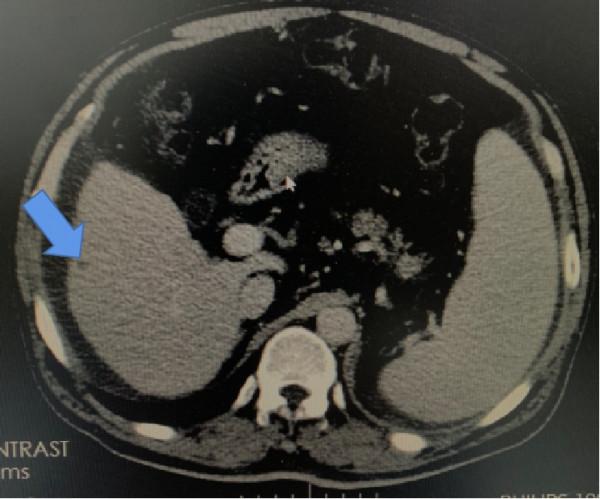

各種單發鈣化灶(如肺內鈣化灶)。鈣化分為生理性和病理性鈣化,通俗地講,人體的某些部分就喜歡鈣鹽沉積,如顱內的松果體,這就是生理性的。

病理性的鈣化,多種多樣,可以是壞死的組織,如結核病,也可以是鈣鱗代謝障礙的疾病等。比如肺內 鈣化灶,其實就是可能過去得過肺炎或肺結核後鈣鹽沉積在壞死組織裡的結果,完全不用管。